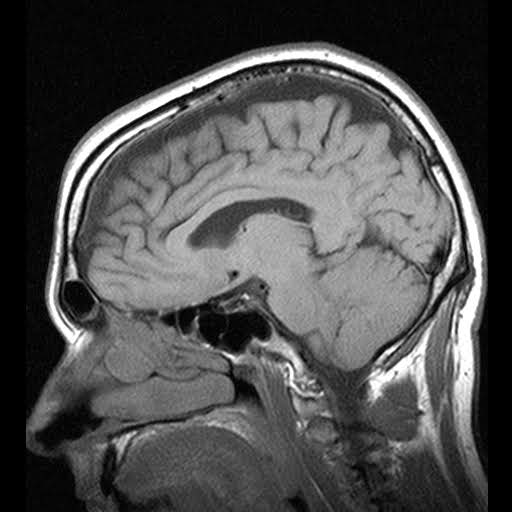

I got an MRI and I have pictures of my brain!

THAT is MY BRAIN!

At least that’s what the office told me when they gave me the disk of pictures. I have no other pictures of my brain with which to compare, and I’ve never seen my brain in person so as to recognize it from these hazy black and white pictures which I’m told came from a big magnet. It remains entirely possible that the pictures on that disk are pictures of somebody else’s brain.

Or that this is a Xerox image of something made entirely of playdough. I can’t prove that it’s not.

It may not be my brain on the disk, and in fact may not be pictures of anybody’s head at all but may be computer-generated. It’s not impossible. If I were asked to prove that the pictures were real I could not do it. I have to take it on faith that the office told me the truth. I don’t have the means or the understanding of the technology to prove a counterfeit MRI from a real one let alone the ability to prove that the pictures came are of my brain and not of someone else’s.